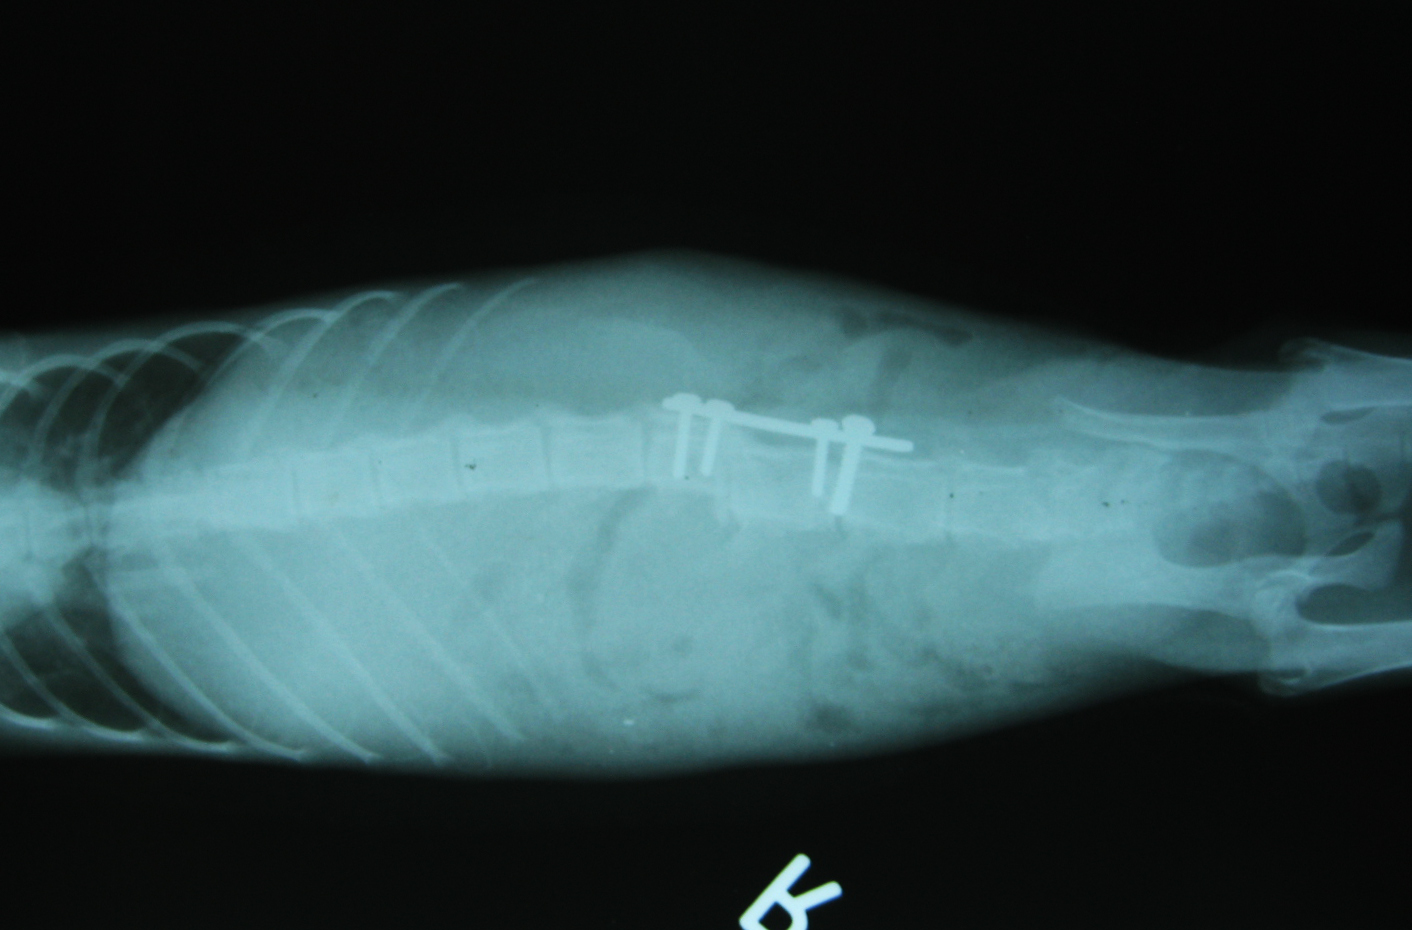

在X光的顯示下,發現小將的脊椎錯位,下半身雖然冰涼但有輕微的痛覺反應,醫生說,有成功再站起的機率,可以努力看看。短短的一句話卻讓我思考了好久,因為,如果他手術後依舊癱瘓,貓咪不但一輩子陷入無法爬起的痛苦中,而且可能還需人工擠尿和擠便,重要的是,原發現的愛心姐姐無法收容他,未來的他該何去何從?

為了讓小將術後能達到最佳狀態,由擅長外科手術聯合醫院的黃醫師來執行,目前恢復情況良好,小將也在大家的期待中自行站立了起來。